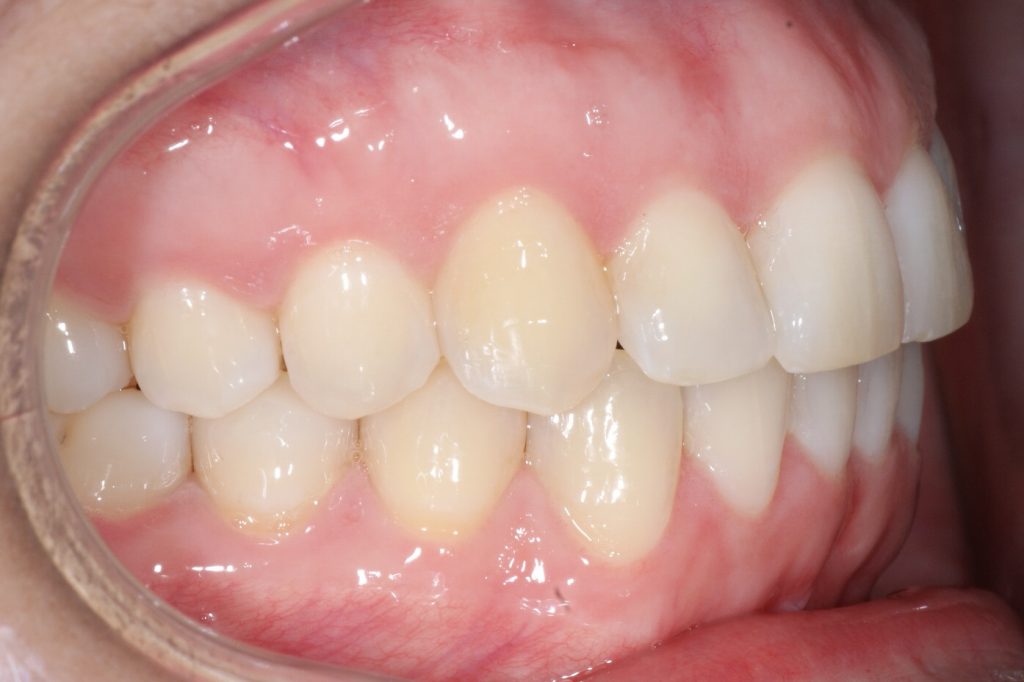

Correction d’une malocclusion de type Classe I, surplombs inadéquats et chevauchement modéré aux 2 arcades.  57 coquilles furent nécessaires pour améliorer ce sourire.  Traitement chez une adulte, réalisé en 15 mois.